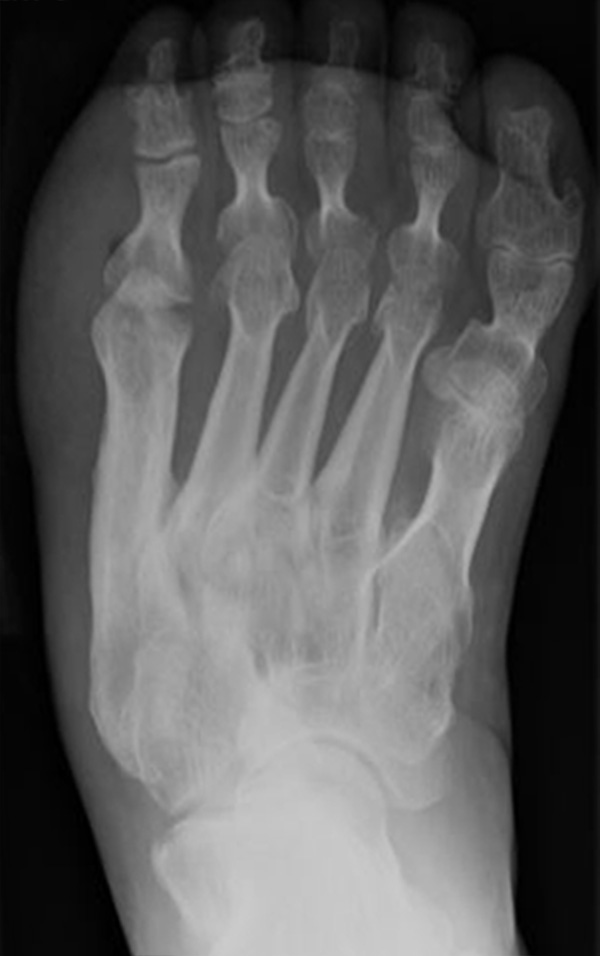

Abb. 3a, b: Präoperatives (a) und postoperatives (b) Röntgenbild bei Korrektur einer Typ I Deformität durch eine Exostosenabtragung.

Abb. 7 a, b: Typ II Deformität mit prä- (a) und postoperativem Röntgenbild (b) mit K-Draht Osteosynthese und gleichzeitiger Hallux valgus Korrektur.

Abb. 8 a, b, c: Typ III Deformität mit prä- (a) und postoperativem Röntgenbild (b, c) mit Schrauben-Osteosynthese.

Abb. 9 a, b: Typ III Deformität mit prä- (a) und postoperativem Röntgenbild (b).